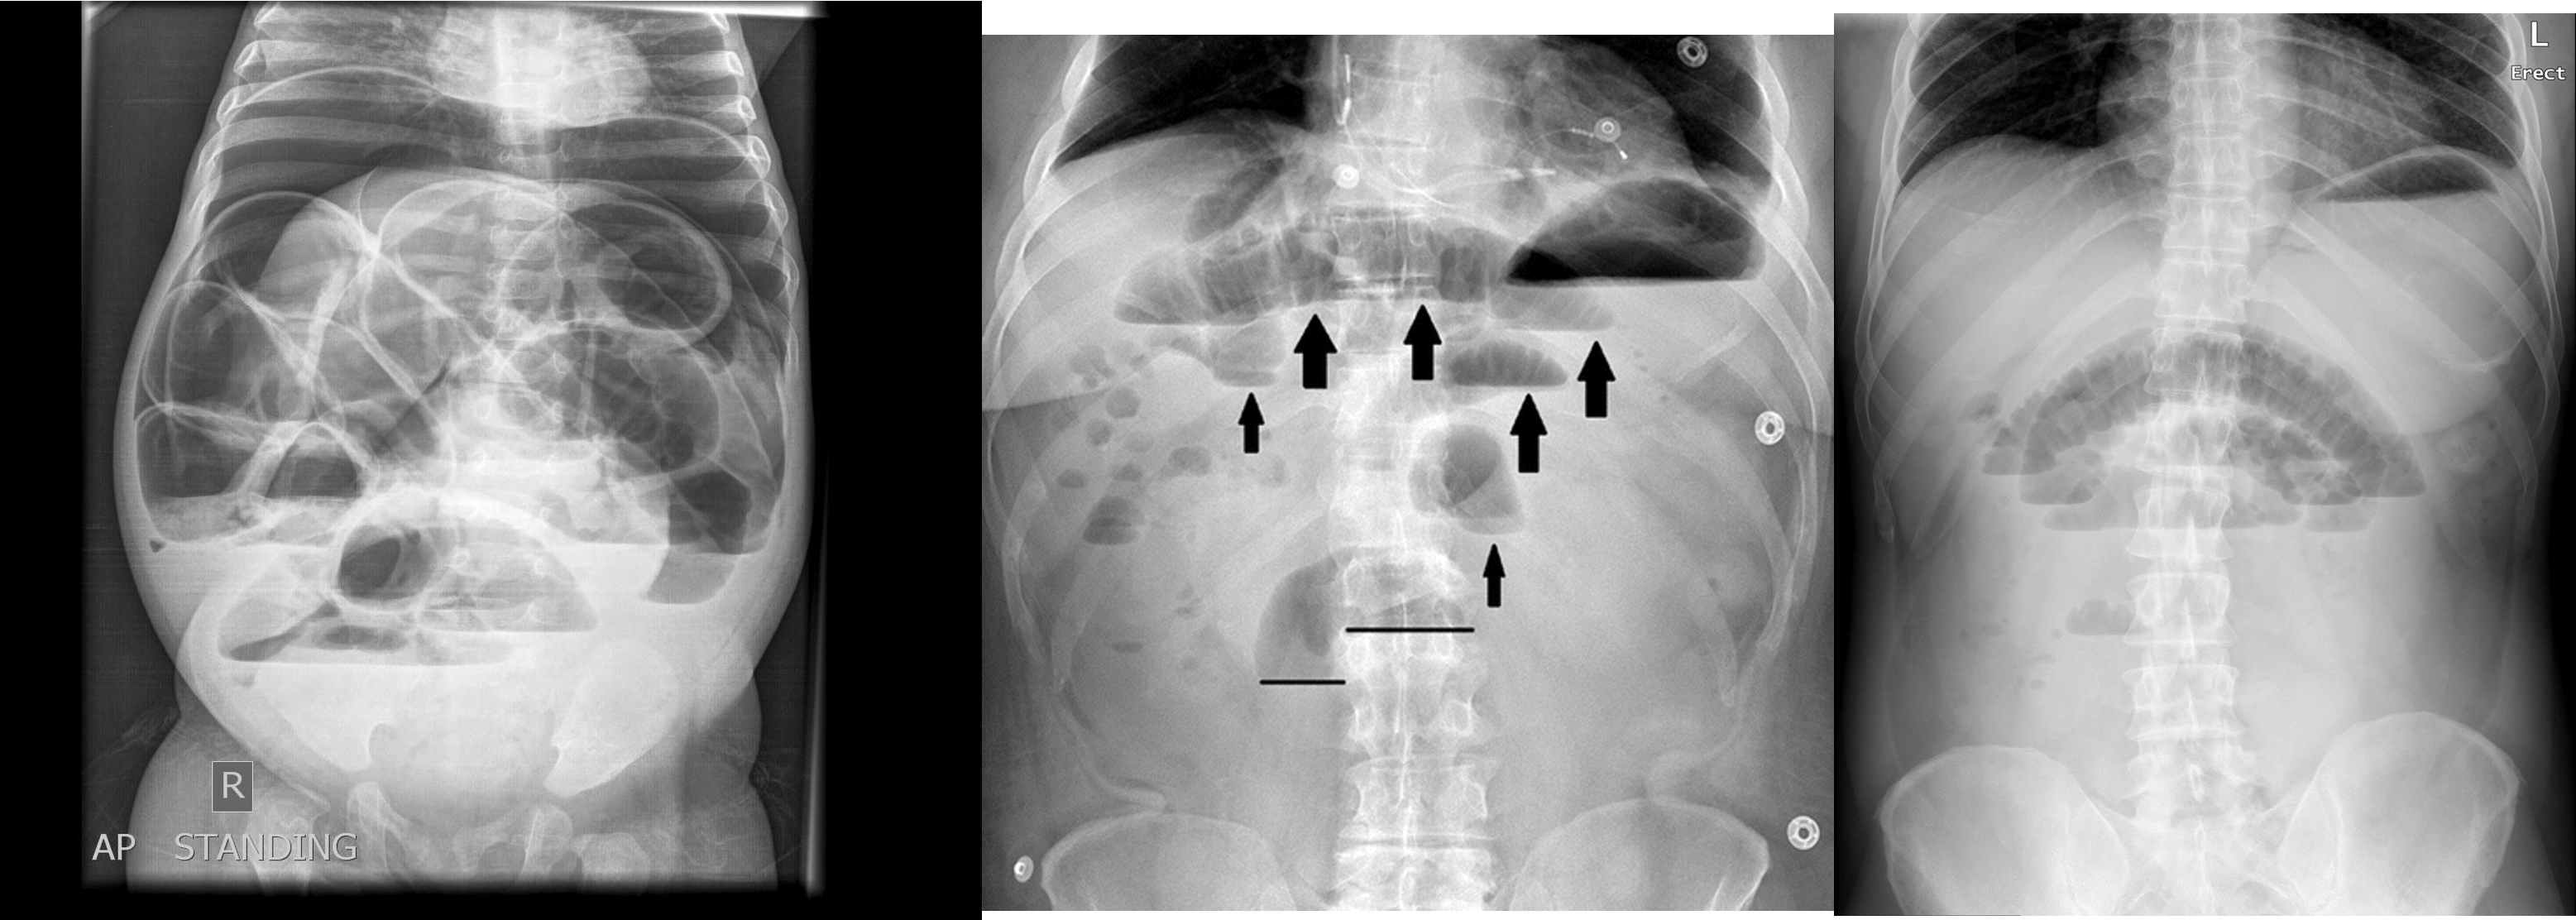

Abdomen Imaging

normal abdominal x-ray - normal gas pattern - lower pole kidney - gastric bubble is found - comment on bone

Free air under diaphragm - most commonly due duodenal perforation - (diff; perforated viscus, peptic ulcer, duodenal, penetrating truama, post surgical 8 days likely to disappear)

- free air

- erect - air fluid levels - should be not more than three - >5 significant 11 found -

- no free air under diaphgram - 8 fluid level, (evidence of bowel obstruction) (adhesion, hernia, IBD; Crohn, cancer, inturcucception, gallstones)

9 air fluids in large bowel - mucosal folds are not completed - highly suggestive of bowel obstruction

- dilated large bowel - mucosal folds are not complete - (diff; cancer, divertuclitis, volvolus, toxic megacolon?)

- if both small and large most likely nonmechanical paralytical illeus

2) Dilated bowel (diff; cancer colon) -

closed loop obstruction from both sides result large bowel most dangerous left side most common cancers

- coffe bean - omega sign - volvulus twisting around its axis - it is closed loop obstruction very dangerous - (treat clonoscopy decompression)

- volvulus

- abdominal x-ray - Dilated colon (diff - cancer colon, ulcerative colittis)

- 8 air fluid - small intestinal central - intistinal obstruction due adhesion - stack of coins. ++ NG tube aspiration relieve from vomitting

- dilated small bowel obstruction - stack of coins

- small bowel

2) large bowel - mucosal issnt complete periphery